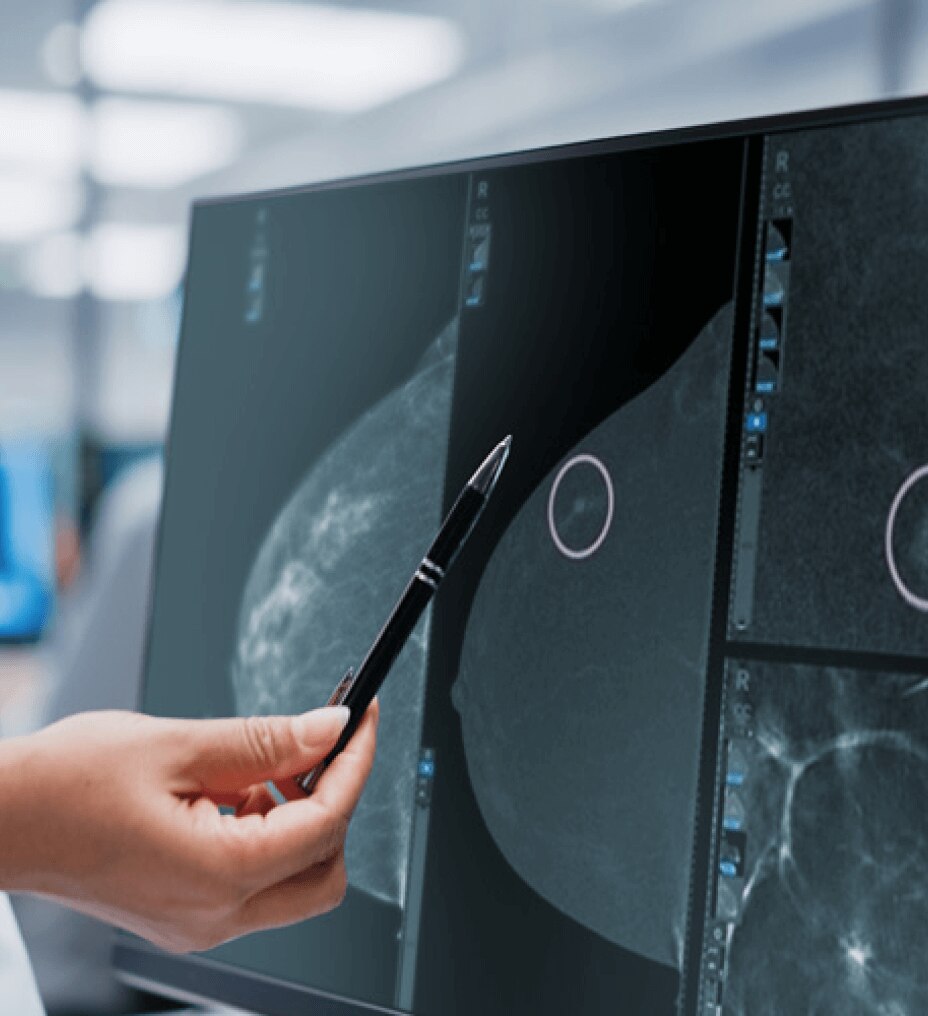

Immagini eccezionali

L'accesso ad AIR™ Recon DL consente una qualità delle immagini e una produttività eccezionali